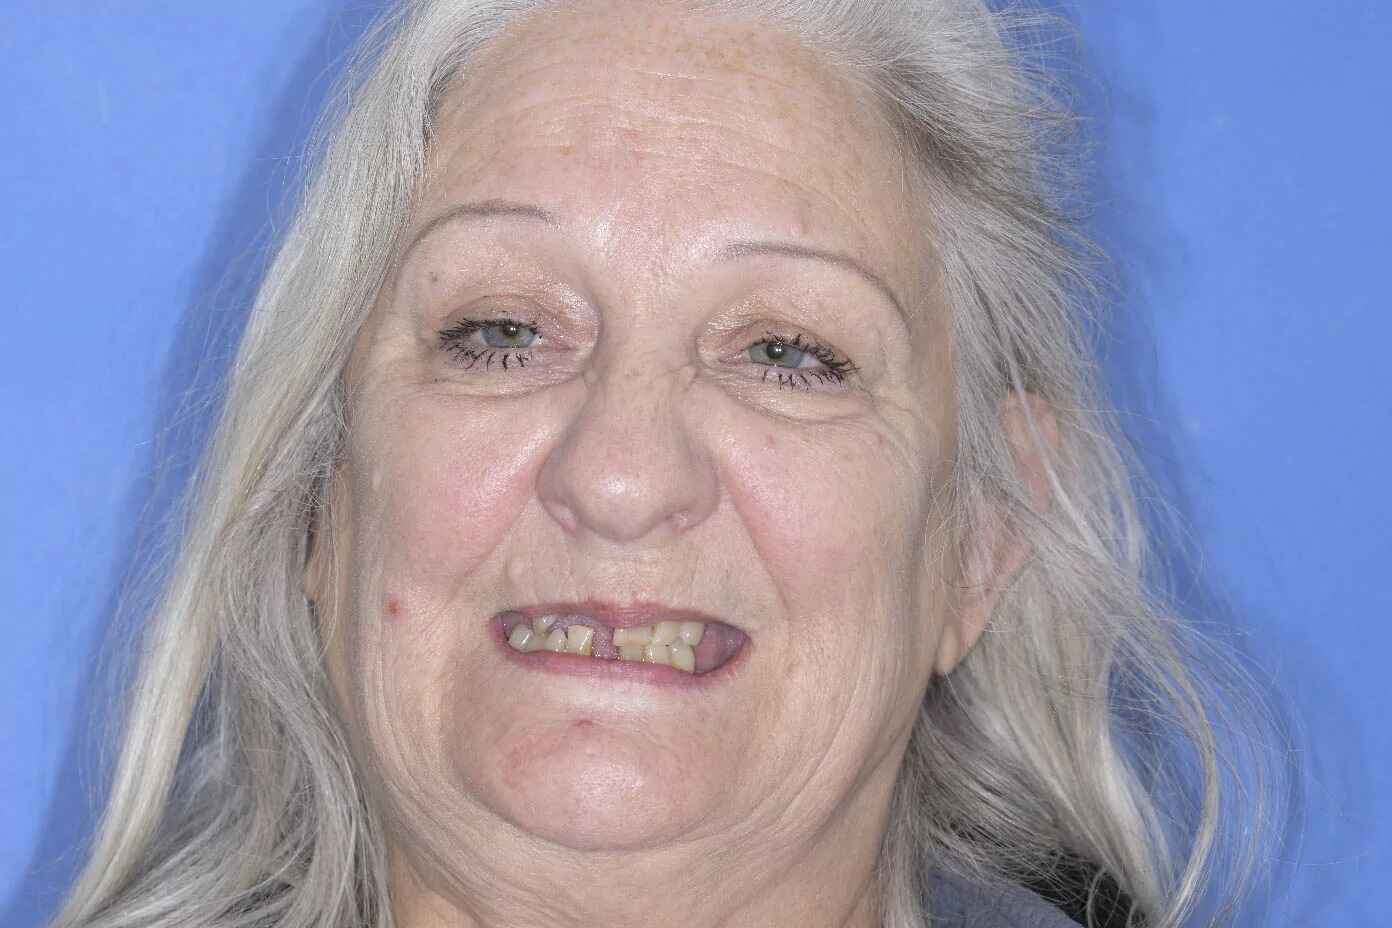

Jill’s Procedure

Jill needed a full mouth rehabilitation of dental implants and tooth crowns.